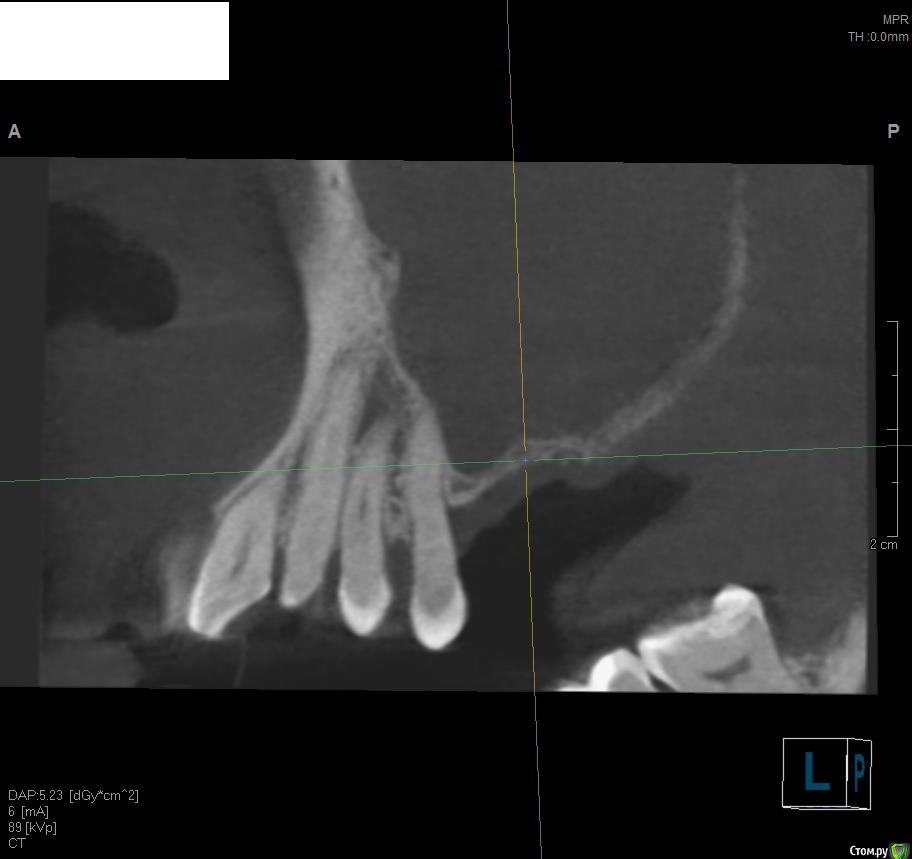

Jurai Опубликовано 19 мая, 2016 Поделиться Опубликовано 19 мая, 2016 Вот такой пациент: Больше года назад выполнена радикальная гайморотомия, с созданием соустья по поводу изменений слизистой в синусе. Сейчас картина такая. Ортопед желает два имплантата, а я что-то в сомнениях - платформы на уровне апексов меня не привлекают. Прошу вашего мнения, что возможно здесь сделать? По поводу непрозрачности синуса - ЛОР дает добро. Ссылка на комментарий

ILGAMSA Опубликовано 19 мая, 2016 Поделиться Опубликовано 19 мая, 2016 Вот такой пациент: Больше года назад выполнена радикальная гайморотомия, с созданием соустья по поводу изменений слизистой в синусе. Сейчас картина такая. Ортопед желает два имплантата, а я что-то в сомнениях - платформы на уровне апексов меня не привлекают. Прошу вашего мнения, что возможно здесь сделать? По поводу непрозрачности синуса - ЛОР дает добро.Бардак.Нужна консультация ЛОР-врача, владеющего FESS. Лучше было бы удалить 15, после заживления растить кость по вертикали, опираясь от костного пика 14 зуба. Да и в остальном наладить гигиену, разобраться с остальными. 1 Ссылка на комментарий

TIGER Опубликовано 19 мая, 2016 Поделиться Опубликовано 19 мая, 2016 5 зуб на выход синус и вертикальная аугментация! Ссылка на комментарий

Bier Опубликовано 19 мая, 2016 Поделиться Опубликовано 19 мая, 2016 по центральному снимку вроде не все уж так плохо. Не знаю правильно ли было бы удалить 5ку... Вертикальный размер можно десной решить.А вот в пазухе печаль. Ссылка на комментарий

faity Опубликовано 19 мая, 2016 Поделиться Опубликовано 19 мая, 2016 в чем провинился 5 зуб ?Корень оголен более 1/2 Ссылка на комментарий